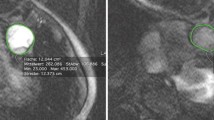

(a) The mean systolic area fraction of reverse flow in a slice in the MPA decreased slightly post-PEA. (b) A cross-sectional slice in the middle of the PA trunk taken during mid-systolic downstroke shows more reverse flow in a representative patient (PH18) pre-PEA than post-PEA. (c) The mean systolic spatially averaged vorticity in the MPA increased post-PEA. (d) Visually this is shown in a representative patient (PH7) pre- and post-PEA with streamlines colored by vorticity during peak vorticity. (e) The mean fraction of positive helicity was approximately half of the MPA volume for the pre/post-PEA group. (f) A cross-sectional MPA slice taken during systole with surface vectors projecting forward moving velocity onto the slice and colored by helicity shows distinct counter rotating structures in the post-PEA (PH18) condition as opposed to the pre-PEA condition. Colored lines (a, c, & e) represent the San Diego classification of the PEA specimens for each patient –blue = Type II, green = Type III, grey = not recorded. *=p < 0.05, **=p < 0.01